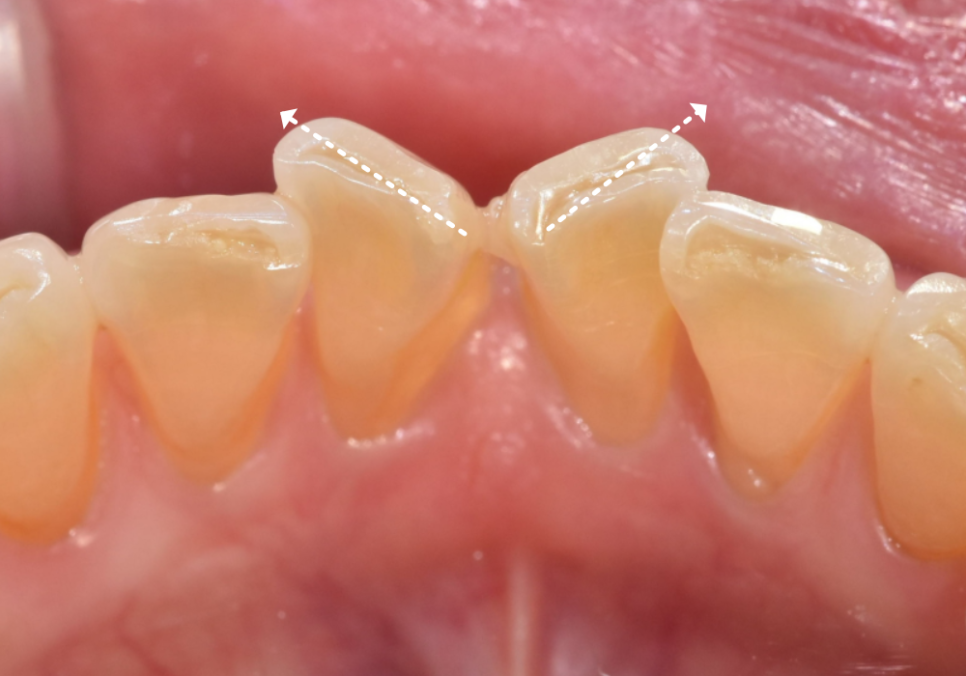

전체적인 치아 배열은 안정적이라,

앞니를 많이 깎아내지 않고도

충분히 배열을 맞출 수 있는 상태였습니다.

전체 치아를 이동시키는 교정 대신,

틀어진 각도만 정교하게

바로잡는 라미네이트로 가닥을 잡았고,

결과적으로 환자분께

가장 만족스러운 대안이 되었습니다.

살짝 틀어져 있던 앞니가 제 자리를 찾고 나니,

미소가 훨씬 단정하고 편안해 보이시죠?